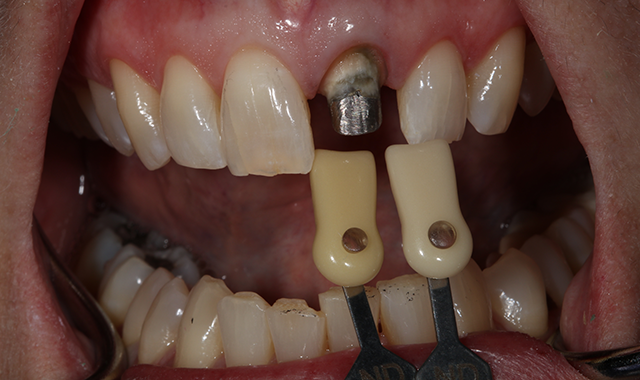

A 60-year-old female presented upon referral from her general dentist for prosthodontic treatment when she requested a new full-coverage crown restoration for tooth #9. She fractured the tooth participating in gymnastics as a child. The tooth was initially restored with composite resin, but when it became discolored, endodontic therapy followed by placement of a cast post, core and crown was performed. The ceramic on the mesial-incisal portion of the crown had fractured (Fig. 1), so the patient reported that it was finally time to replace it.

Fig. 1 Fig. 2

The patient also reported that she was never happy with the restoration, and she also was unhappy with the incisal chipping on tooth #8. Since she was about to embark on a new career, she wanted a smile she felt confident about.